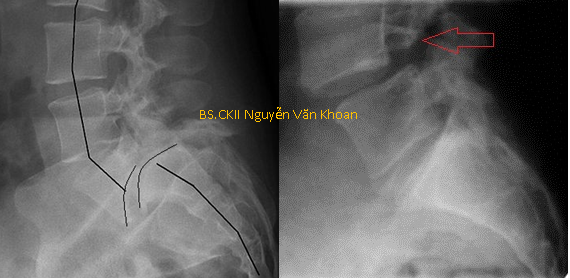

Hình X quang trên cho thấy trượt đốt sống nặng L5/S1 (hình bên trái). Trượt đốt sống L4/L5 do khuyết eo L4 (hình bên phải).

Trượt đốt sống do khuyết eo đốt sống mức độ nặng và trượt đốt sống do loạn sản đốt sống là một dạng khác với trượt đốt sống mức độ nhẹ do khuyết eo đốt sống. Gọi là trượt nặng khi di lệch hơn 50% bề mặt thân đốt sống. Trượt nặng thường kèm theo gù vùng thắt lưng-cùng. Trượt nặng hiếm gặp hơn trượt nhẹ, trong các trường hợp trượt đốt sống do khuyết eo đốt sống thì trượt nặng chỉ chiếm dưới 10% và thường gặp ở lứa tuổi thanh thiếu niên.